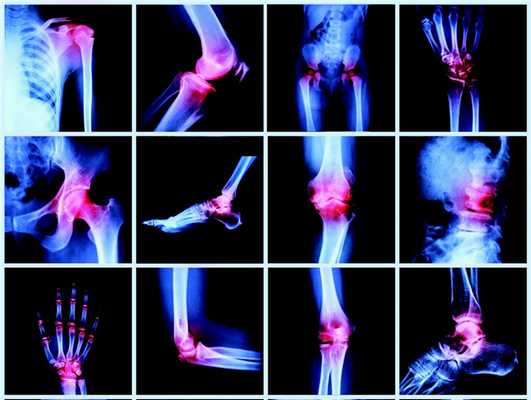

Ревматология – раздел медицины, занимающийся диагностикой, профилактикой и лечением ревматических заболеваний, а именно – воспаления суставов и соединительной ткани. Врачи Юсуповской больницы проведут полный комплекс мероприятий, направленных на улучшение состояния поражённого ревматизмом организма.

Ревматические поражения имеют ярко выраженные болевые симптомы, к которым относятся:

- Припухлость, боль и тугоподвижность в суставах, мышцах и костях;

- Скованность во всем теле и боли в позвоночнике;

- Слабость организма и ломота в теле после перенесённых ангин и вирусных заболеваний;

- Длительное, беспричинное повышение температуры;

- Скачкообразное настроение, слабость и снижение трудоспособности.

Симптоматика ревматических заболеваний весьма разнообразна, так как поражен весь организм. При первых подозрениях на ревматизм, нужно своевременно обратиться к врачам Юсуповской больницы для подробной диагностики и своевременного лечения.